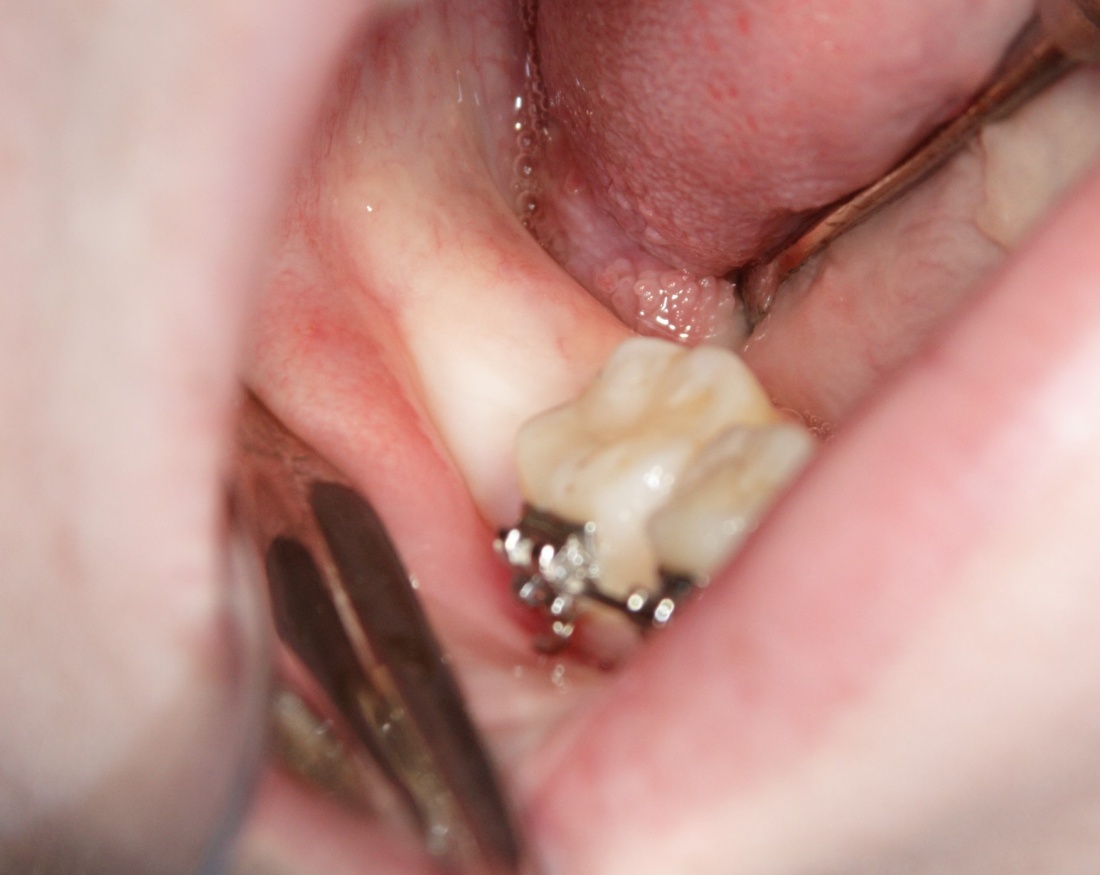

В полости рта все выглядело примерно вот так:

Я прошу прощения за качество фотографий — это было несколько лет назад, тогда мы не придавали фотографии какого-либо значения. Да, собственно, и сейчас не особо придаем))).

Итак, на фото вы видите шестерку и наклеенные брекеты. Последние несколько осложняют нашу работу, существует риск, что мы случайно один из брекетов оторвем — и об этом мы предупреждаем нашу пациентку.